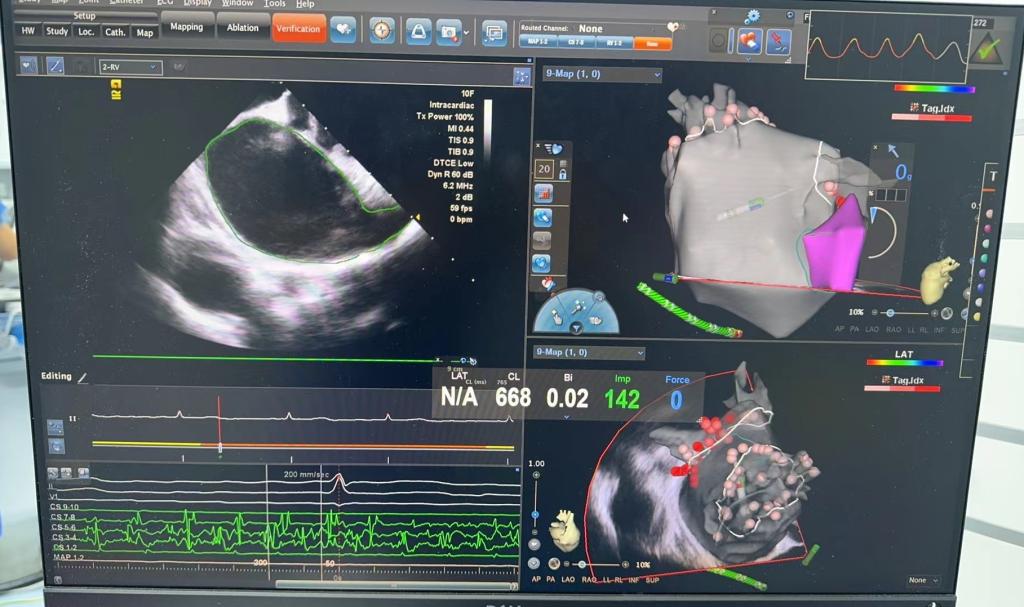

心内科介入团队经过充分讨论和病情分析,决定采用ICE指导下房颤射频消融术,术中进行的房间隔穿刺、左心房建模、导管射频消融等操作均在ICE引导下完成,手术过程顺利,术后患者恢复窦性心律,手术全程极低射线,做到真正的安全绿色电生理。

运用三维系统和ICE完美结合,不仅可以实时监测导管与心肌的贴靠,还能够很好地显示心脏内特殊解剖结构,ICE在心脏介入治疗和电生理检查中具有良好的应用前景,在ICE指导下可以实现零射线或极低射线量的房颤血栓筛查、导管放置、房间隔穿刺及消融等一系列的操作,还可以在左心耳封堵、一站式手术、房缺、肥厚性心肌病等多领域有极好的运用,为患者带来更高效、更安全、更绿色的手术体验。(文图:叶才盛 审核:颜程光 周臻 彭晓露)